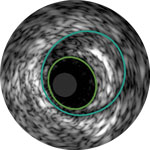

Lumen

Eccentric fibrotic plaque with deep calcium nodule

Acoustic shadowing

Vessel size: 5.5 mm diameter Plaque morphology: Fibrotic plaque with intimal and medial calcium Plaque geometry: Eccentric lesion Guidewire position: True lumen

Quick-Cross catheter: Confidently cross challenging morphologies Phoenix deflecting atherectomy: Front facing to cut, capture and clear mixed morphologies, including calcium; deflecting capabilities for larger luminal gain AngioSculpt scoring balloon: Score calcium to reduce dissection4 Stellarex DCB: Designed for performance in calcium